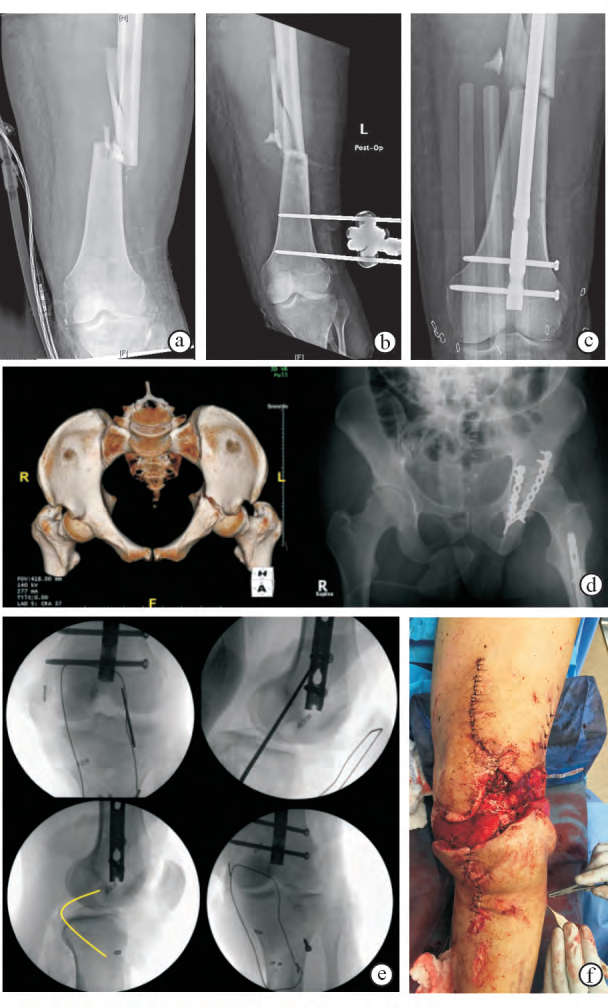

a.急诊X线片显示左侧膝关节脱位合并股骨干骨折;

b.清创术后X线片显示膝关节和股骨复位、外固定架固定;

c.伤后第6天X线片显示外固定架拆除后髓内钉固定股骨骨折;

d.伤后第10天进行髋臼切开复位内固定,左图为术前骨盆CT三维重建影像,右图为髋臼骨折复位内固定术后骨盆正位X线片;

e.伤后第16天进行后交叉韧带、后外侧复合体和髌韧带重建,术中透视影像显示重建时的固定方法;

f.术中照片显示腓肠肌内外侧头肌瓣转移覆盖膝前创面,供日后植皮